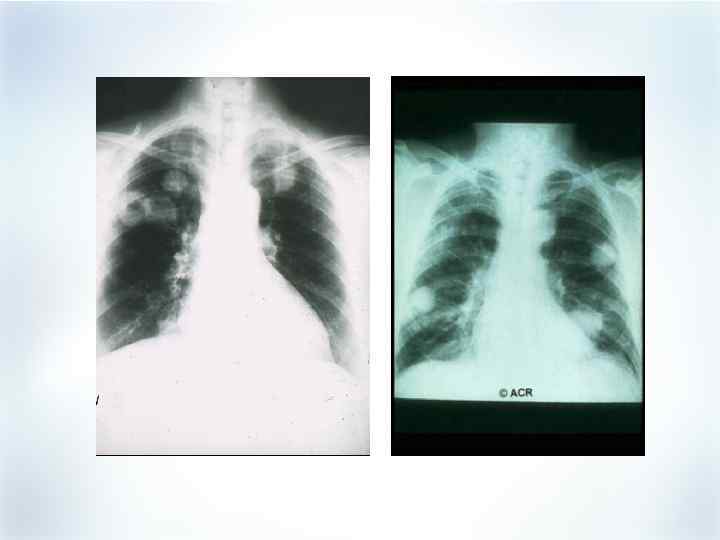

Поражение легких при РА § § § Диффузный интерстициальный фиброз легких (ДИФЛ) Альвеолит Гранулема (ревматоидный узелок) Плеврит (сухой или экссудативный) Облитерирующий бронхиолит (крайне редко)

Поражение легких при РА § § § Диффузный интерстициальный фиброз легких (ДИФЛ) Альвеолит Гранулема (ревматоидный узелок) Плеврит (сухой или экссудативный) Облитерирующий бронхиолит (крайне редко)